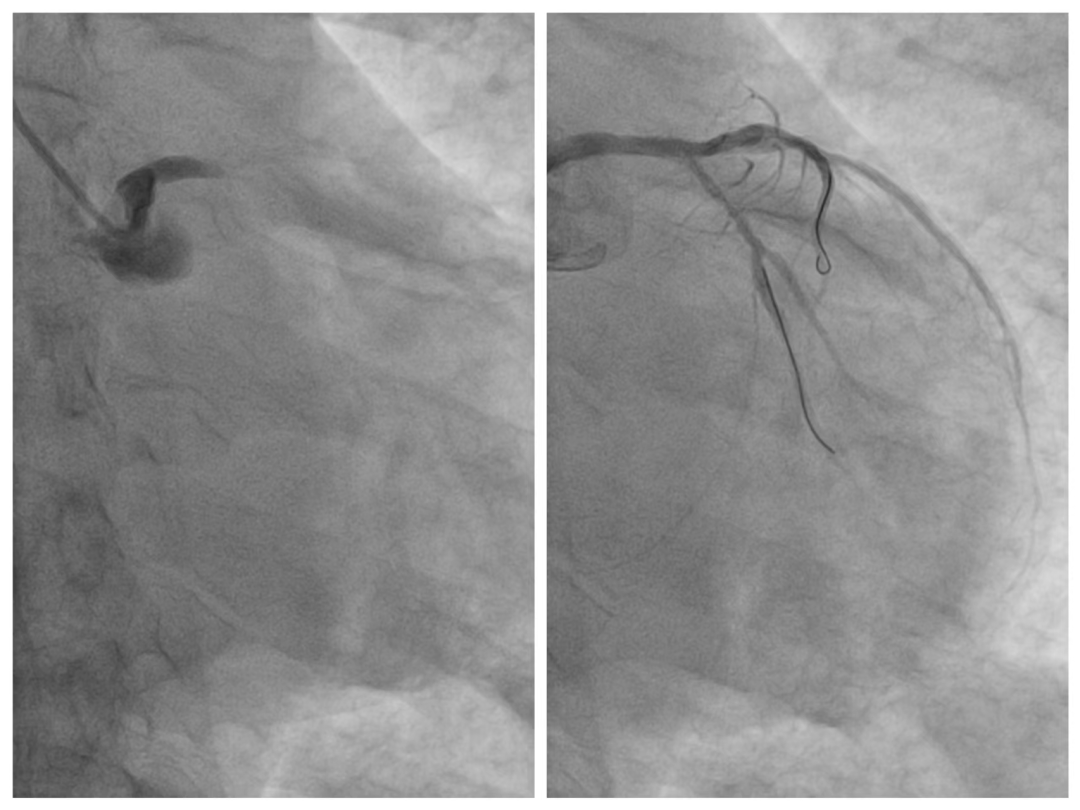

如此危重的病情,黄大爷正面临着生命危险,时间就是生命,时间就是心肌,来不得半点犹豫,我院胸痛中心陈丽媛主任医师、仇昌智副主任医师团队立即为患者开通救治绿色通道,第一时间将患者送到介入室,为患者紧急开通闭塞的血管。在左主干-前降支开口(LM-LAD)植入一枚药物支架,同时植入主动脉球囊反搏(IABP)加强循环支持治疗,整个救治过程流畅快速。手术过程顺利,仅48分钟的时间,闭塞血管便得以开通,术后,将患者送到重症监护室进一步密切监护。

▲术前(左图)左主干中段后完全闭塞,术后闭塞血管得以开通(右图)